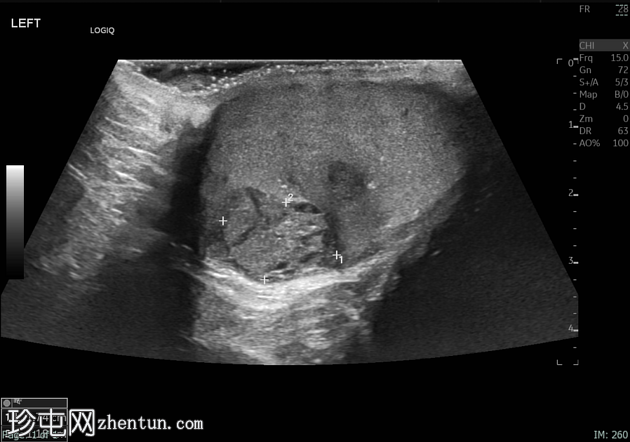

超声检查

/ 横切面

2.png

左侧睾丸肿大,体积约56 mL,可见弥漫性微结石,以及三个内部等回声病灶,伴囊性变、微钙化和明显血流信号,最大病灶大小约4.8 x 3.2 cm。

未见腹主动脉旁或髂淋巴结肿大。